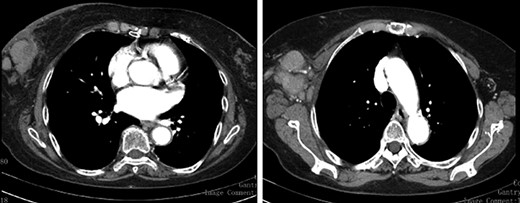

We present an 88-year-old female patient with past medical history of pulmonary tuberculosis, peripheral venous insufficiency and asthma. There was no personal or family history of cancer, namely breast cancer. The patient was referred due to a lump detected in the right breast. On observation, the patient presented with a palpable mass in the transition of the external quadrants of the right breast with 50 mm in diameter, hard, mobile, non-adherent to the skin or the underlying tissue, as well as a suspicious axillary adenopathy. A mammogram was performed and the lesion was described as a nodular lesion with lobulated contours, with 44.5 × 24.5 mm and associated skin thickening (Fig. 1). On ultrasound, the lesion corresponded to a hypoechoic nodule with lobulated and poorly defined contours as well as with multiple ipsilateral axillary adenopathies, the largest with 20 mm—breast imaging-reporting and data system (BI-RADS 5). A core biopsy of the breast lesion and suspected axillary adenopathy were performed, both consistence with diffuse large B-cell lymphoma, positive for CD20, BCL2, BCL6 and MUM1 (Fig. 2). Nuclear immunostaining was observed in about 90% of neoplastic cells. On staging CT scan, no lesions were found than those already described (Fig. 3). The patient was submitted to R-mini-CHOP (CHOP and Rituximab), completing three cycles, with clinical and radiological response.

Staging CT Scan—lobulated mass associated with exuberant ipsilateral axillary adenomegalies.